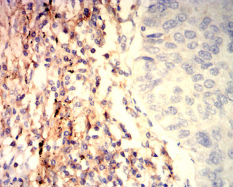

IHC    1/200-1/1000